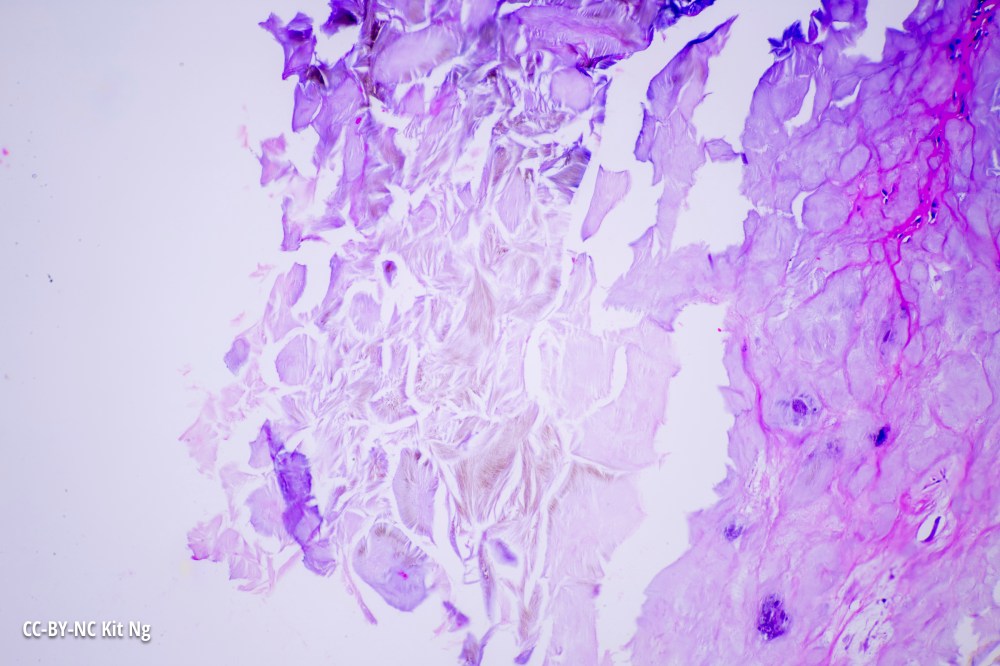

Second field showing gout crystals from the same human specimen. (TM: 100x, picture taken with a Zeiss 10x Planapo on a Sony A7ii)